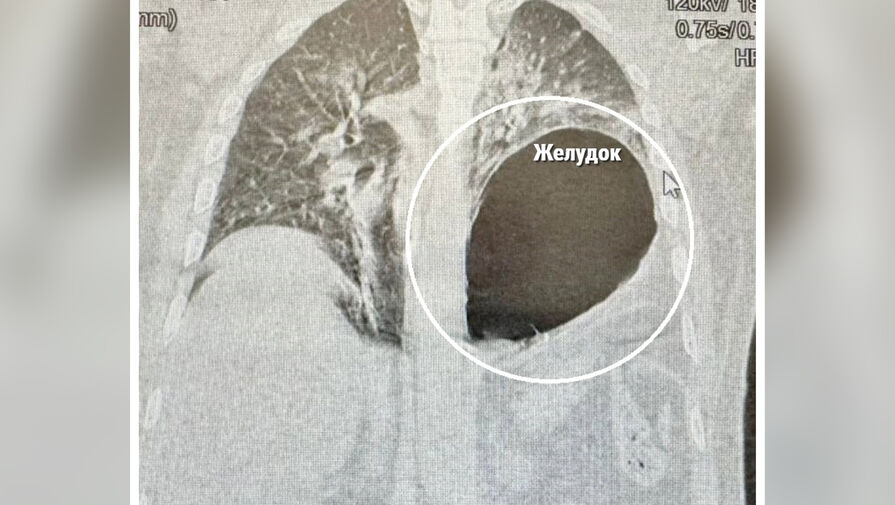

На момент поступления в медучреждение пациент с трудом двигался и дышал. Диагностика показала, что у него закрытая травма груди и живота, перелом нескольких ребер, разрыв диафрагмы со смещением желудка в плевральную полость.

«Левое легкое спалось, а желудок практически переместился в плевральную полость и сдавил сердце и средостение. Развился шок, и счет шел на минуты. Мы выполнили экстренную лапаротомию, низвели желудок, дренировали левую плевральную полость и ушили дефект диафрагмы», — рассказал хирург больницы Сергей Поликарпов.